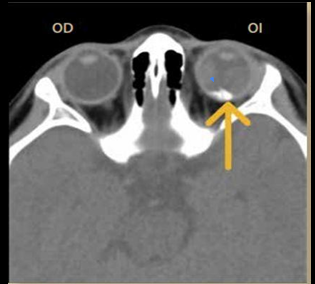

Tc en orbitopatia tiroidea

Agrandamiento músculos extraoculares, exoftalmos, nervio óptico estirado

TC en exoftalmos

Protrusión ocular anormal

Disociación índice globo ocular - línea intercantal